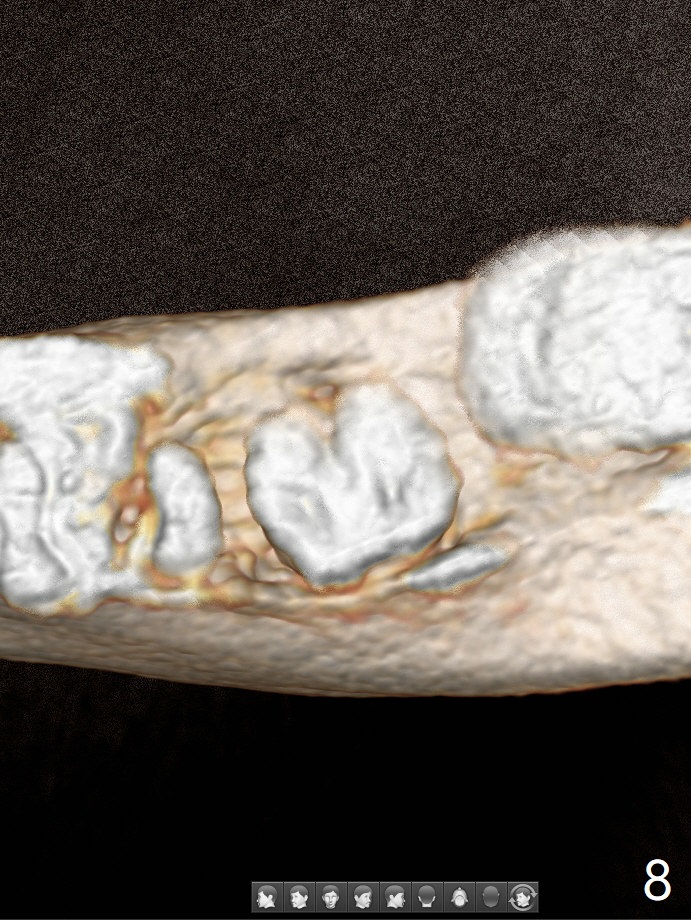

A 44-year-old woman has severe chronic periodontitis. The tooth #18 is nonsalvageable (Fig.1). To avoid distal end guide, do not remove the 3rd molar in the lab. While a 5x7.3 mm implant is long for the site (Fig.2), a 5.5x5.5 mm one seems to be a better option (Fig.3). The latter could be 1 mm more coronal. The last drill (5.0 mm) and cortical tap will be used free hand. #17 will be extracted after implantation. Since the patient is reluctant to have #16 to be extracted, place #18 implant ~ 1-2 mm more distal so that the implant crown will have some occlusal contact with #16. Prepare IS extra wide kit. Or use a 8/7 mm trephine bur to harvest cortical bone from the ramus. Drill a hole for fixation screw before removing the onlay graft. Keep the 3rd molar if possible. Prepare Tatum spacers to measure the size of #18 socket opening. In fact, the lab is able to place a 5x7.3 mm implant with 2 thread exposure buccal. Prepare sticky bone and PRFx2 to prevent periimplantitis. Soak one O-ring in case of having to extend osteotomy by .5 mm (next longer drill (1.5 mm) - 1 mm (O-ring)). For socket shield at #18 (Fig.6 *), section the tooth horizontal with a new surgical fissure bur (Fig.4 black area), use an end-cutting bur to remove buccal edge of the root (Fig.5 red area) and finally remove the lingual portion of the root (Fig.6 pink). Insert 4.5x10 mm dummy implant to determine whether the final implant 5x7.3 mm (bottom of the 1st line) will probably contact the shield. Buccal view of the lingually inclined 2nd molar (Fig.7). After removal of the crown of the 2nd molar (Fig.8 occlusal view), the lingual portion of the root is resected (Fig.9 black area). CT coronal sections show socket shield formation (Fig.10,11).